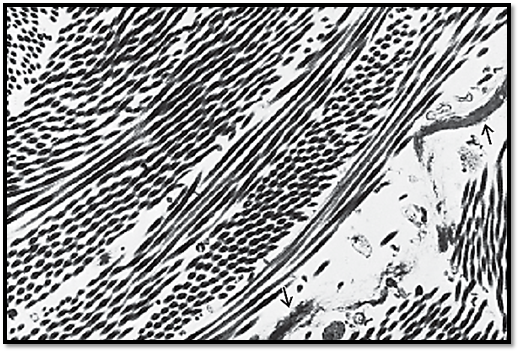

Collagen fibers are the main portion of the structural intercellular elements. While fresh, the fibers are shiny white. In light microscopic images, the fibers look like strands of hair curling in spirals. In thin sections for electron-microscopic examination, they are inevitably cut in different planes and directions. In this figure, the fibril bundles are cut either across or longitudinally, but mostly tangentially. Lengthwise-cut fibrils faintly show periodic cross-striation. There are also elastic fiber elements . Collagen is the most widely found protein; by weight it represents about 25% of the protein in the human body. Bundles of collagen fibrils from the stratum papillare of the corium.

Electron microscopy; magnification: × 10000